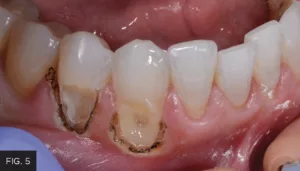

Following the laser tissue removal, a #0 retraction cord with ferric sulfate was placed to further hold the tissue in place and keep the area moisture-free. Although the tissue was isolated and retracted, there was some minimal bleeding present, which prevented a completely dry field. Retraction paste (3M™) was placed around both tooth preparations and completely covered the recently lasered tissue and cord. (FIG. 5) The retraction paste was allowed to set for 5 minutes. The paste was gently rinsed off to prevent rebound bleeding and the area was dried.